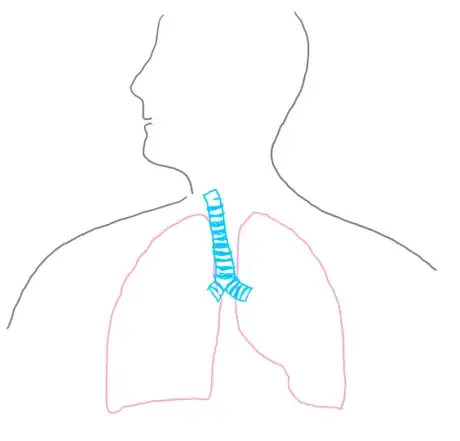

5Outline the trachea and bronchi trunk. Using your lungs as a reference, draw an upside-down Y shape centered at the top quarter of the lungs and leading upward to the neck. The center point should be at the suprasternal notch, and the long part of the Y should extend to the Adam’s apple. This Y shape is the two bronchus trunks and the trachea. These structures are cylindrical with notches similar to what you would see on a tin of soup; adding this detailing is beneficial to your viewer because it allows them to better understand the physiology of the structure.